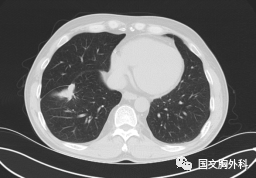

這個(gè)病人檢查胸部CT如圖3:根據(jù)影像學(xué)考慮是惡性腫瘤,行手術(shù)治療后病理回報(bào):“肺膿腫,合并炎癥纖維組織增生”,因此“肺占位”不代表就是惡性腫瘤,診斷金標(biāo)準(zhǔn)是病理診斷。如果檢查后發(fā)現(xiàn)“肺占位”先不要驚慌,及時(shí)就診請(qǐng)專科醫(yī)生會(huì)診指導(dǎo)治療才是關(guān)鍵。